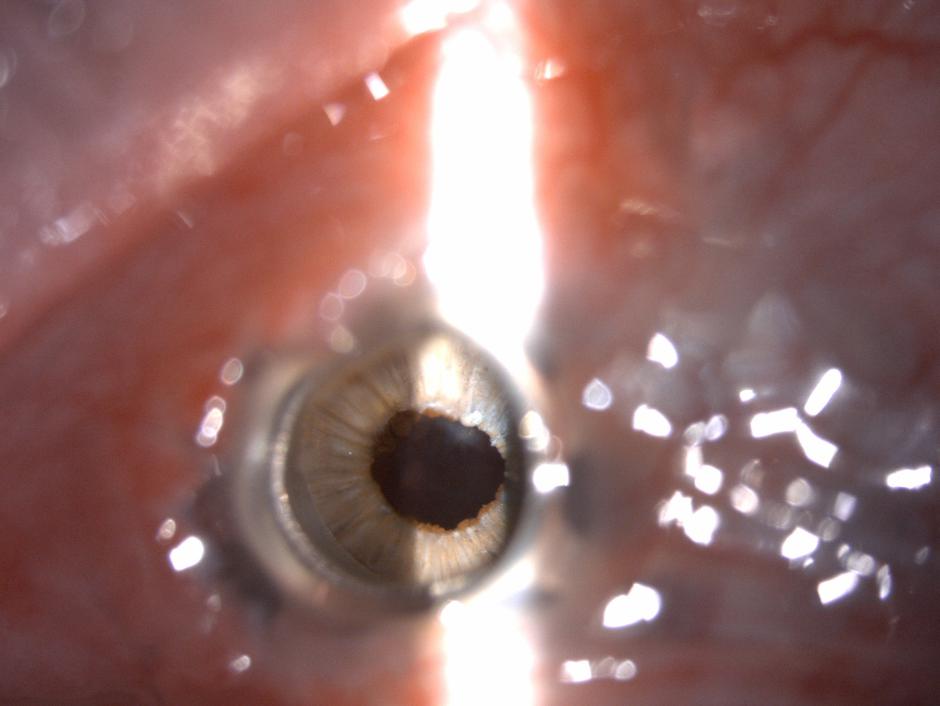

Oko pred posegom | Avtor: UKCLJ UKCLJ

operacija zenice | Avtor: UKCLJ UKCLJ

operaija zenice | Avtor: UKC LJ UKC LJ